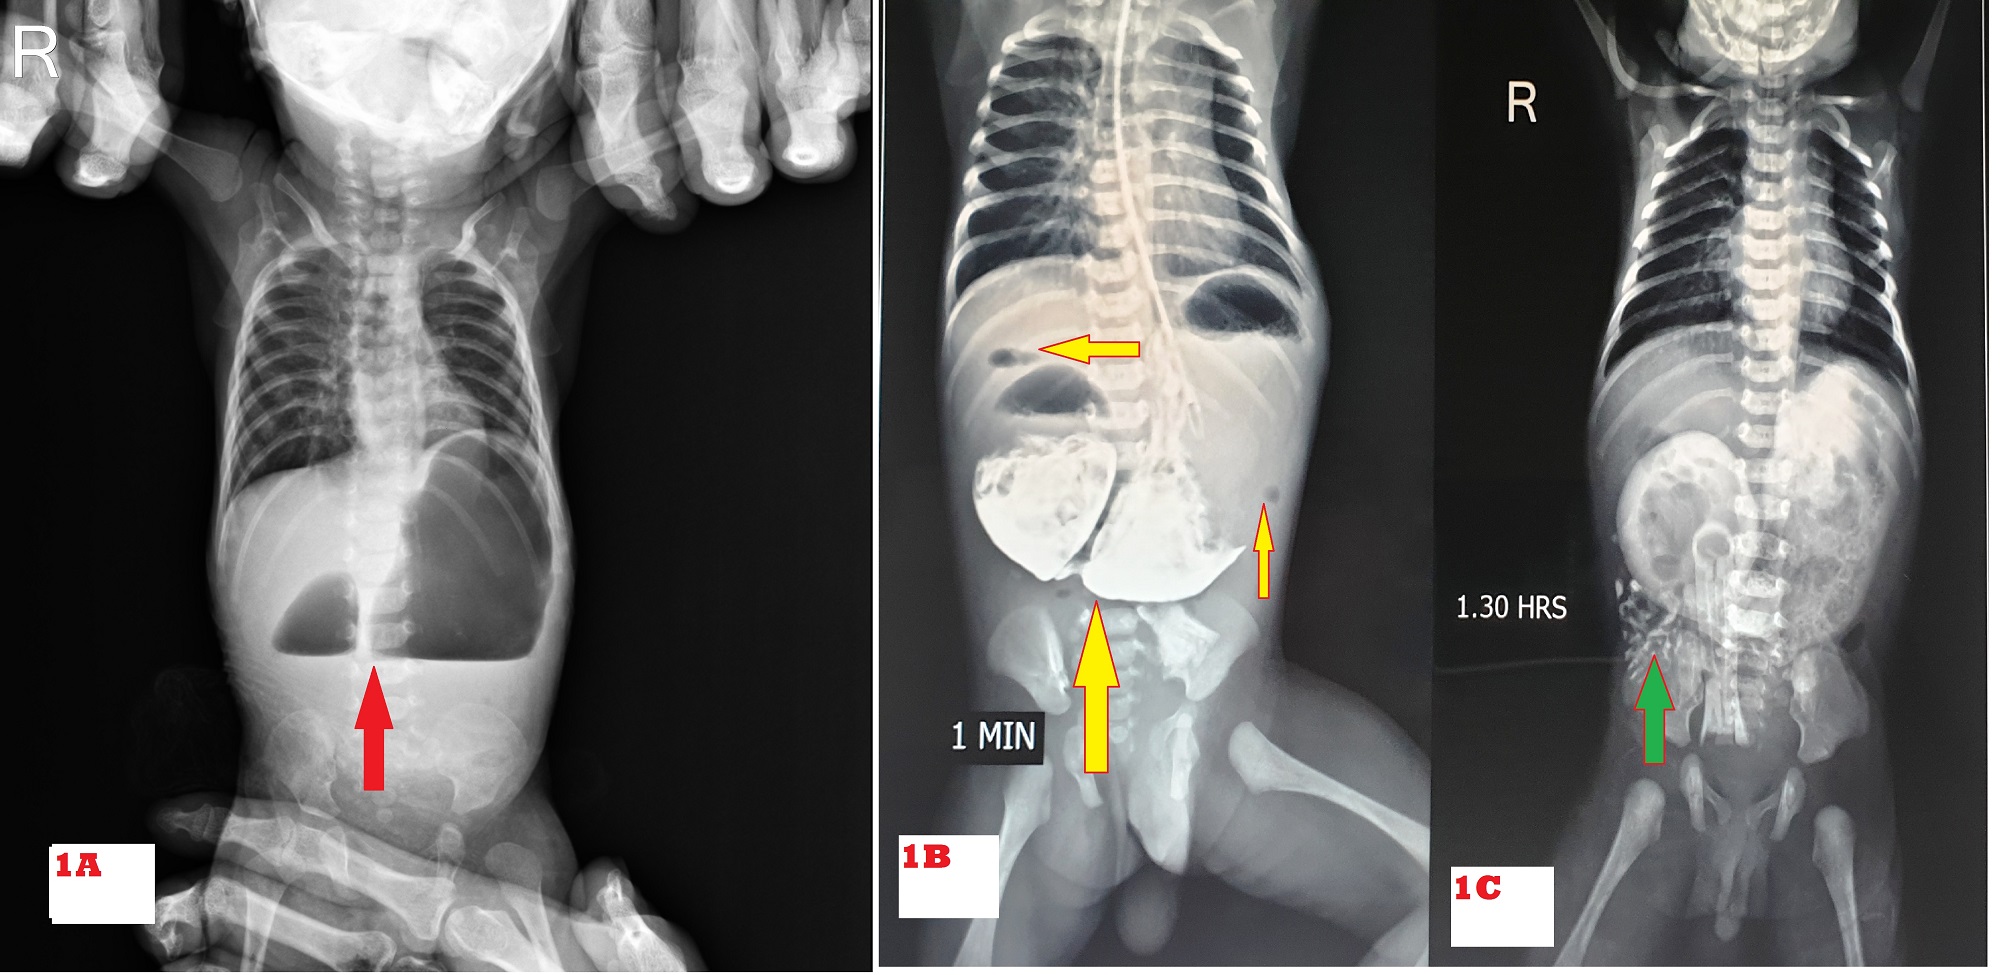

A) Double bubble sign (Red arrow). B & C) Gastrografin upper GI contrast study- hugely dilated stomach and duodenum with intrinsic obstruction as a smooth and rounded end at D2 with distal air (yellow arrow)/ contrast (green arrow) without distal beaking effect into D3.

Of 67 patients, 39 were male and 28 were female with a male to female ratio of 1.4:1. The demographic characteristics of the patients are shown in Table. 1. The common presenting features on presentation were vomiting in 59 (88%) of which 44 had bilious and 15 had non-bilious vomiting, and epigastric bulge in 52 (77%) (Fig. 2). Double bubble appearance on X-ray abdomen was seen in 54 (81%) (Fig. 1A). Seven infants had distended stomach and duodenum with gas in the small bowel on abdominal x-ray. Abdominal USG color Doppler was done to rule out malrotation. Six underwent a gastrografin upper GI contrast study which gave suspicion of the perforated duodenal web (Fig. 1B, 1C). One patient underwent Upper GI endoscopy which showed windsock deformity with a small hole on the web along with a foreign body. The inability to insert stiff red rubber catheter beyond 10 cm per orally with double bubble appearance on of babygram was observed in 7 patients. A single bubble was found in 5 cases. In the patient with IEA, the diagnosis of CIDO was made during feeding gastrostomy, in which the infant feeding tube was not negotiable beyond the second part of the duodenum; moreover, the stomach and duodenum were dilated and filled with bile mixed mucus.

Preoperative X-ray abdomen showing a double bubble sign is diagnostic of duodenal obstruction. It was sufficient to diagnose 54 (81%) patients in this study. Duodenal web with hole (centric or eccentric) was diagnosed by gastrografin meal follow-through in 6 patients and in one by UGI endoscopy.